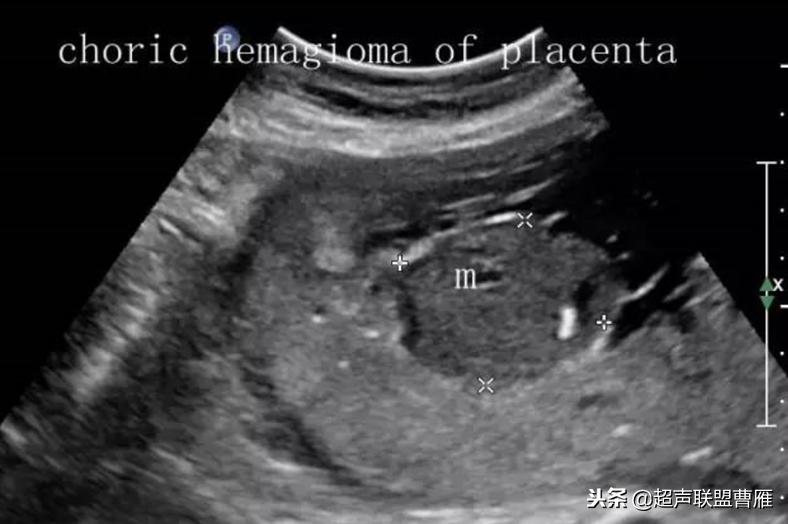

2. 超声表现:胎盘内近胎儿子面可见实性肿物,有时凸向羊膜腔,根据其组织结构,毛细血管瘤和海绵状血管瘤回声偏低,纤维血管瘤回声增强。有时合并胎儿发育异常,羊水过多。

超声诊断要点

(1)是胎盘里的实质性肿块

(2)可以高回声或低回声

(3)肿块往往靠近脐带插入处

(4)整个妊娠时间,肿块大小往往无明显改变

(5)约三分之一胎盘绒毛膜血管瘤合并羊水过多。

(6)彩色多普勒可以发现肿块内有血流信号